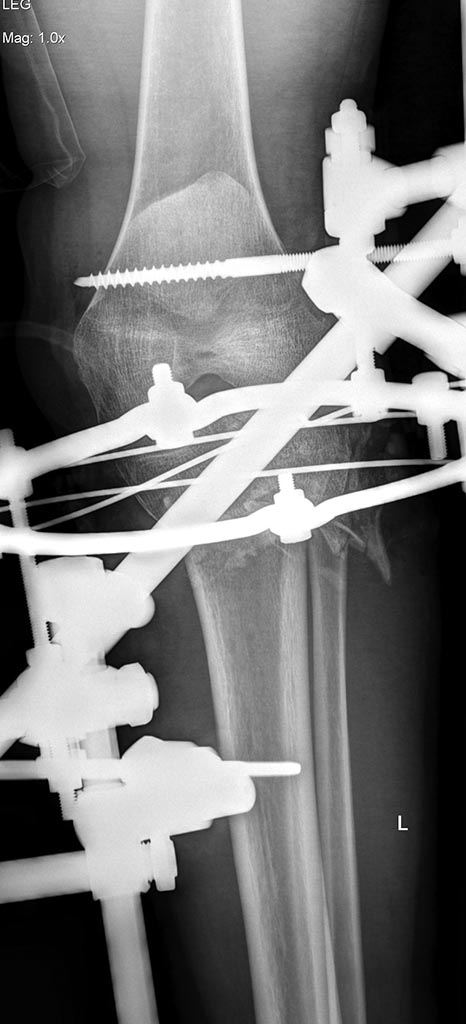

Имеется: Закрытый перелом диафиза левой локтевой кости. Закрытый оскольчатый перелом диафиза левой бедренной кости в средней трети. Открытые (3a-b) оскольчатые внутрисуставные переломы проксимального отдела обеих костей правой и левой голени. (см. снимки)

При поступлении выполнено: ПХО открытых перелом костей правой и левой голени, фиксация в аппаратах; фиксация перелома левой бедренной кости в аппарате; иммобилизация левого предплечья лонгетой.

Планируем: при неосложненном заживлении, остеосинтез правой большеберцовой кости пластиной; остеосинтез бедренной кости стержнем; локтевой кости пластиной.

Что делать с переломами костей левой голени пока не решили окончательно. Пока мнение коллег такое: оставить все как есть до заживления /консолидации и ортопедические проблемы с коленным суставом и укорочением (3-4 см) решать в отдаленном периоде – эндопротезирование (?).